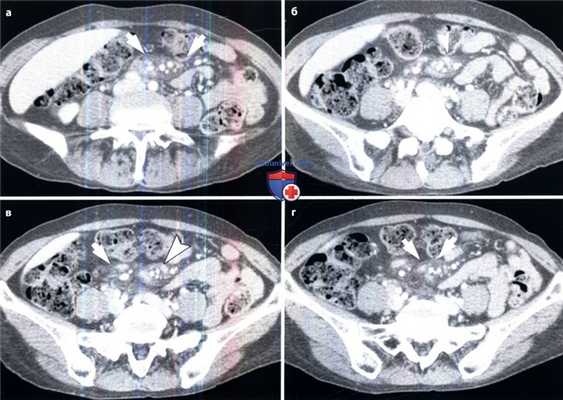

Гематомы брыжейки у пациента на фоне антикоагуляционной терапии.

(а, б) На аксиальных КТ-срезах, полученных до введения контраста, определяется четко отграниченное объемное образование в брыжейке. Внутри этого образования находится область высокой плотности (указатели). Измеренная плотность этой области составляет от 35 до 50 единиц Хаунсфилда.

(в, г) На аксиальном и корональном КТ-срезах, полученных в венозную фазу контрастирования, визуализируется объемное образование (стрелки) в брыжейке, часть которого имеет высокую плотность и не накапливает контраст. Повреждение брыжейки и гематомы у пациента, пострадавшего в ДТП.